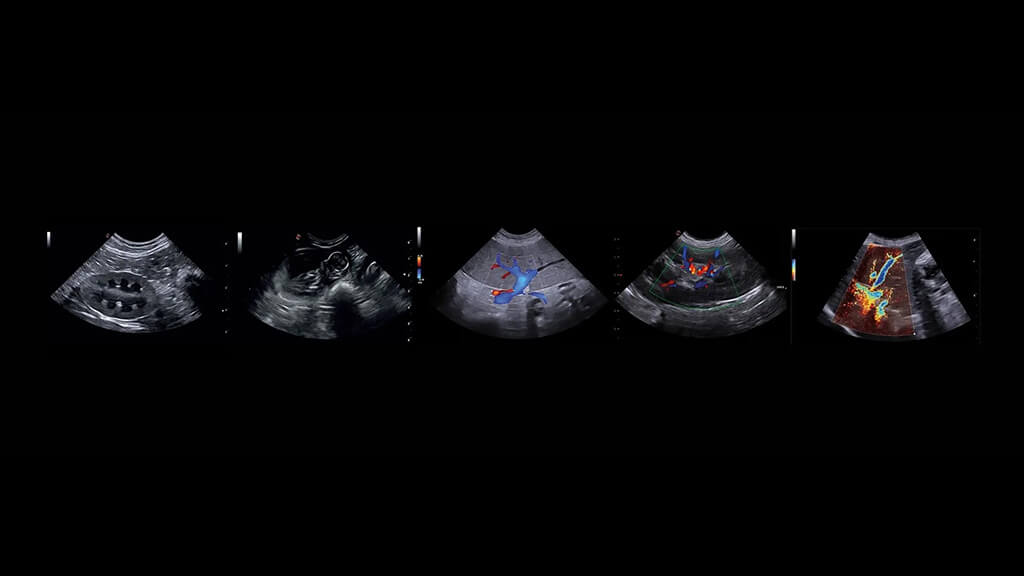

EKO; köpekler, kediler ve uygun olgularda egzotik türler dâhil olmak üzere pek çok hastada güvenle uygulanabilir. Başlıca kullanım alanları:

1) Doğumsal Kalp Hastalıkları

• Patent Ductus Arteriosus (PDA)

• Ventriküler Septal Defekt (VSD)

• Atriyal Septal Defekt (ASD) ve diğer doğumsal anomalilerin saptanması ve hemodinamik etkilerinin değerlendirilmesi

2) Edinsel Kalp Hastalıkları

• Mitral kapak hastalıkları

• Dilate Kardiyomiyopati (DCM)

• Hipertrofik Kardiyomiyopati (HCM) gibi sık görülen kardiyak hastalıkların tanısı ve evrelemesi

3) Perikardiyal Hastalıklar

• Perikardiyal efüzyon

• Kalp tamponadı gibi acil müdahale gerektirebilen durumların hızlı değerlendirilmesi

4) Kitle ve Tümöral Yapılar

Kalp içinde veya çevresinde yer alan kitlelerin görüntülenmesi ve fonksiyonel etkilerinin analiz edilmesi

5) Basınç ve Volüm Yükü Değerlendirmesi

Kalbin sistolik ve diyastolik fonksiyonlarının incelenmesiyle; hastalığın ilerleyişi, yüklenme bulguları ve klinik riskin belirlenmesi